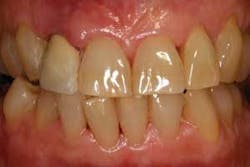

The first patient (see Image 1) was a 63-year-old, white female with no significant medical history. She presented with a buccal abscess between the maxillary right lateral and central incisors. Radiographically, there was evidence of a fracture and decay on the lateral and resorption on the central (see Image 2).

Both teeth were deemed hopeless and slated for extraction. Provisionalization was a challenge as the patient declined wearing a removable appliance, and the adjacent virgin teeth would have required preparation to support a fixed provisional. We elected to extract the teeth, place immediate implants with a narrow-diameter implant in the lateral position (see Image 3), graft between the implant and the extraction site, and place two prefabricated zirconia abutments, which were tightened to 35 Ncm (see Image 4).

The majority of the abutment preparation was performed extraorally. The provisional was relined and luted with a semi-permanent cement (Durelon). Centric and excursive contacts were removed. The patient was advised to adhere to a soft diet and avoid forces to the surgical site. When comparing the patient at the completion of the procedure (see Image 5) and six weeks postoperatively (see Image 6), the soft-tissue levels were maintained. The impression for the final prostheses was made six months following implant placement. Two single Procera AllCeram (Nobel Biocare AB) crowns were then fabricated.